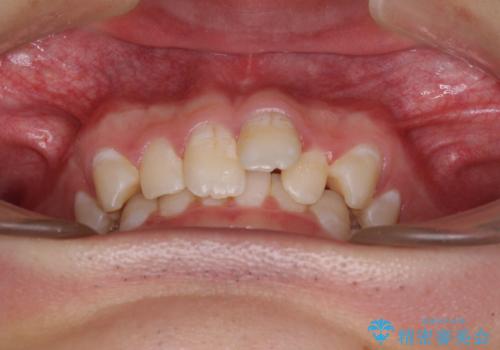

- 強い咬み合わせと前歯のデコボコを気にして来院された患者様です。

下顎前歯が全て隠れてしまうほどの深い咬合で、左右の奥歯は1歯対1歯で咬み合う状態でした。